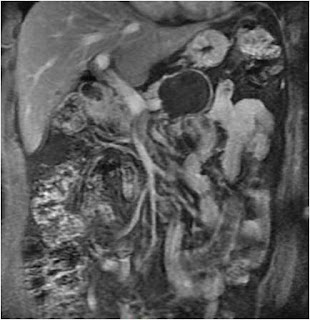

The patient was further investigated with contrast enhanced abdominal magnetic resonance imaging (MRI) of the abdomen which showed a well defined, large (> 5 cm) unilocular cystic lesion with thick enhancing capsule located centrally in the body of pancreas. There was no duct – cyst communication (Figure 1 & 2).

Figure 2